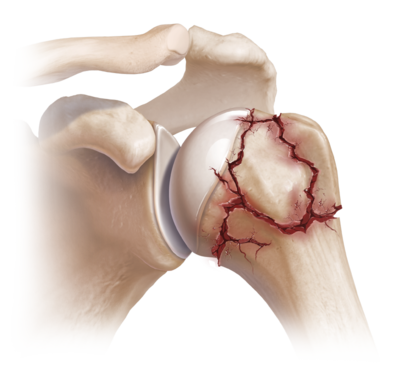

- Osteosynthese